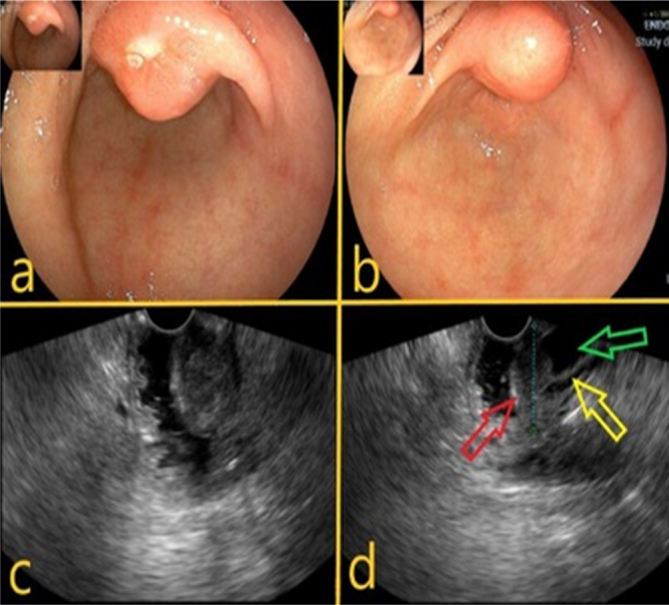

Mixed neuroendocrine-non-neuroendocrine tumors (MiNEN) are a rare type of tumor formed by two components, a non-neuroendocrine component that is most often an adenocarcinoma and a neuroendocrine tumor, and each of these components must represent at least 30% of the tumor. The origin of this tumor on the ampulla of Vater or periampullary region is more infrequent. Usually, the lesions are highly aggressive and quickly metastasizing, and their biological behavior is dictated by the high grade of the neuroendocrine component. This is the first report of a patient with ampullary MiNEN treated employing a robotic pancreaticoduodenectomy. Although being submitted to aggressive treatment with complete surgical resection followed by systemic therapy, the patient developed early recurrence with hepatic metastatic disease, demonstrating the hostile nature of these tumors.